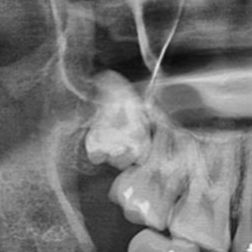

깊이 박혀 있는 상악 매복 발치가 축농증 위험이 있다고 들어서 망설여집니다. 최근 들어서 종종 통증 있고 신경 쓰이는 정도라 뽑고 싶기는 한데 많이 위험할까요? 안 뽑고 놔두면 염증이 생기거나 옆 치아가 상하진 않을지 궁금합니다. 꼭 뽑아야 하는지, 뽑는다면 얼마나 고난이도일지 여쭤봅니다!

사진으로만 봤을 경우에는 사랑니 주변에 상악동에는 큰 문제가 있는 것으로 보이지는 않습니다.

상악동이라는 위턱에 있는 공간을 침범해 있는 사랑니의 경우 발치 중 천공이 일어나고 축농증이나 상악동 염증으로 이어질 가능성도 있긴 합니다. 발치 후에는 출혈을 막고 최대한 빨리 치유가 될 수 있도록 콜라겐 덩어리를 삽입하는 것이 축농증 방지에도 도움이 됩니다